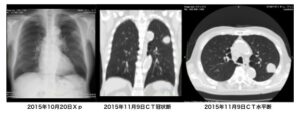

左からBクリニックで撮影された胸部X線写真、その5日後にC病院で撮影された胸部CTの矢状断、水平断です。

C病院で撮影されたCTの水平断には、長径10㎜程度の楕円形の陰影が見てとれます。C病院の担当医は、これを見逃しました。

ところで、Bクリニックの先生が注目した胸部X線写真での腫瘤影は、わたしには到底、判読できません。CTの水平断でみられる陰影を、矢状断で確認して、それと胸部X線とを比較して……とやってみますが、やっぱりよくわかりませんね。この単純X線写真で肺がんを疑ったB先生と、CTを撮影しても肺がんを発見できなかったC病院の担当医との差は、いったいどういうことでしょう。